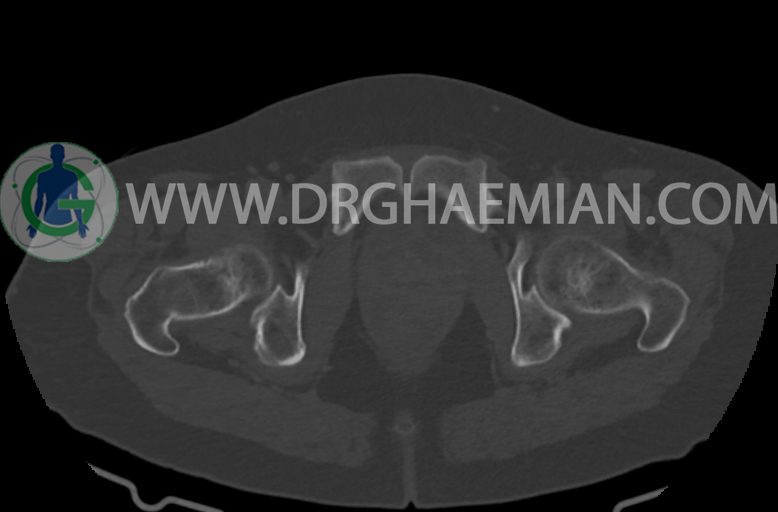

–ساختار Cystic multiseptate همراه با Enhancing thick septation به ابعاد 79x62mm در

لگن دیده می شود که در درجه اول مطرح کننده ی ضایعات نئوپلاستیک تخمدانی نظیر mucinous cyst adenocarcinoma است.